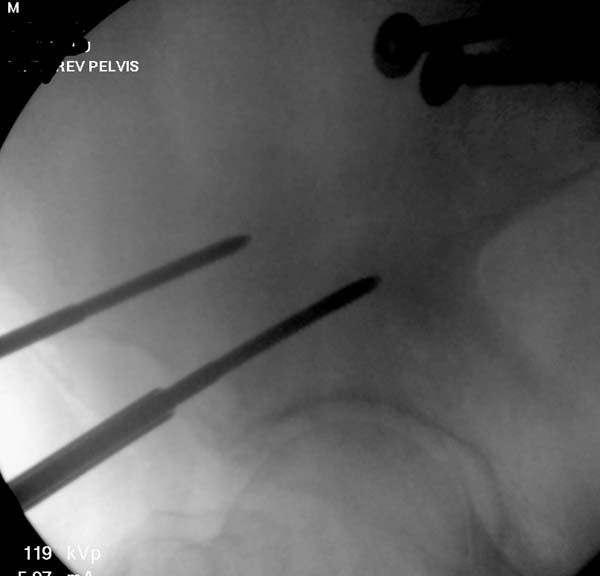

Здесь снимки, которые показывают направление стержня, а также идею

репозиции вытяжением. На рентгенопроницаемых столах имеется возможность

установить дополнительную раму, где по желанию можно увеличить или

уменьшить высоту угла вытяжения. Для репозиции таза больной в положение

на спине, стержень для вытяжения остается во время операции. Система

подойдет для тракции головки бедра из вертлужной впадины, и для этого

стерильная веревка и Synthes Universal Chuck with T-Handle.